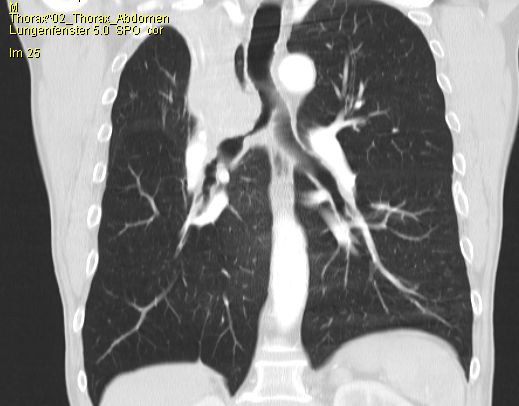

57-jährige Frau mit einem primär cerebral

metastasierten Adenokarzinom im rechten Oberlappen![]() | |